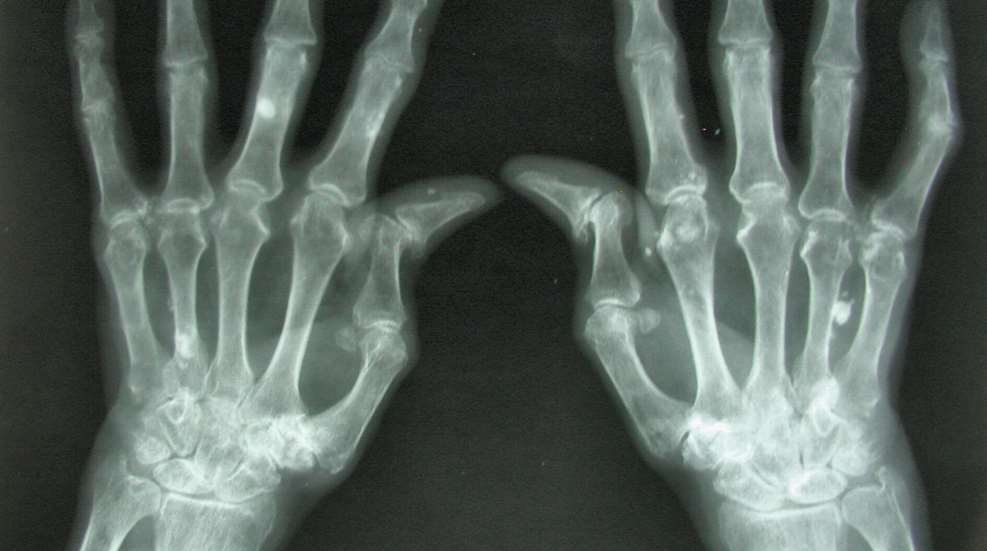

When you have arthritis, gripping a pistol can be like holding the handle of a jackhammer wrapped in barbed wire. Merely assuming your grip or trying to mitigate the gun's recoil can cause "Uncle Arthur" to flare up. But why? The pain originates from the fact that a shooter must exert considerable force to support the weight of the pistol, and to provide the stability needed for accuracy. Such forceful contractions of muscles can increase pressure on the inflamed joints of the fingers and hands. There's also the fact that the range of motion required to grasp a roughly tubular object of a relatively small diameter is actually quite large. The effect is strongly dependent on an individual’s personal characteristics such as hand size, finger length and strength, but in general, the smaller the diameter of the object to be grasped, the greater the demand on the joints to generate motion...which leads to greater pain. Here are some tips to help make that more manageable.